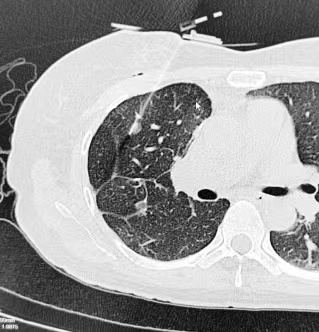

手术用时半小时。术中采用局部麻醉,患者无明显不适,未出现气胸、血胸等并发症。术后观察,患者无特殊不适,顺利返回病房。术后1天复查胸片无特殊即安排出院。